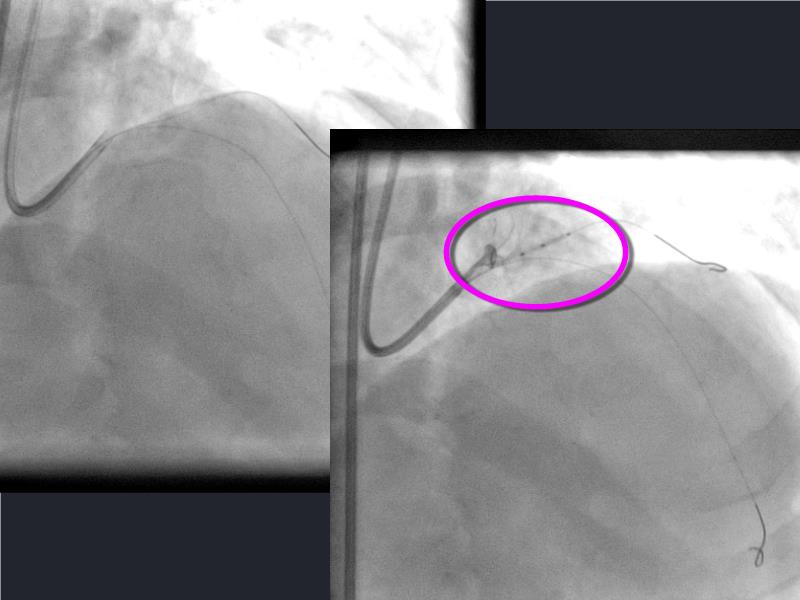

- To understand novel tools and techniques for effective management of bifurcation lesions and long diffused lesions using dedicated stenting solutions